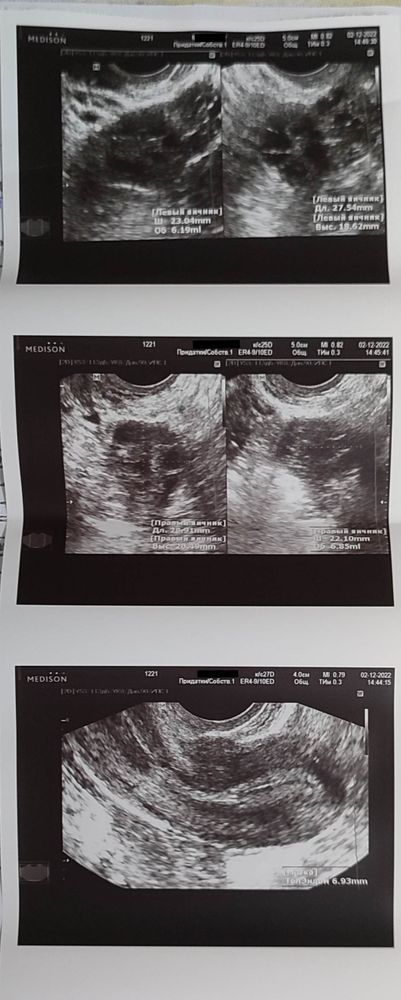

Далее 2 декабря я попала на УЗИ в ЖК(результат 3-4 фото), там узист сказала , что последствия овуляции она не видит, что возможно её совсем не было, матка у меня совсем маленькая и будут проблемы с зачатием и беременностью, посмотрела на результаты платного УЗИ, посмеялась и сказала что никакого доминантного фолликула она по этому УЗИ не видит, короче говоря очень меня расстроила и нагнала жути.

Тут объем матки 12-13 куб.см. Нормы от 40куб.см.

Из - за длительного приёма кок иногда такое бывает. Но по идее все уже должно были восстановиться.